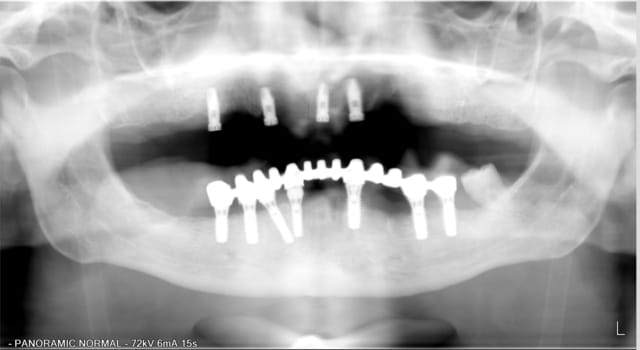

aujourd'hui on a des lésions importantes autour de 13 mais pas de perte de volume de tissu gingival, ou tres peu mais je ne pense pas pouvoir réenfouir (SPLINE)

par contre, les implants en 36/37 sont amha perdus...

A mon avis, si tu ne démontes pas la prothèse, c'est à terme l'implant 33 que tu vas perdre.

Pour le haut je pense demander un scan pour voir comment mettre un implant supplémentaire secteur 2 et aussi juger de la possibilité de combler autour de13 pour si possible conserver cet implant.

En bas j'hésite entre essayer de percer des puits d'accès pour dévisser le bridge avec les piliers afin de tenter de sauver 36/37 mais j'y crois pas trop ou couper en 35 et ROG mais sans support "piquets de tente " pour la membrane je vois pas trop ce que je vais régénérer.

Les trois périmplantites sont du même coté, coté gauche vers lequel la ligne médiane entre les deux apophyses géni semble décalée .

Est ce qu' il ne faudrait pas reprendre l( occlusion du complet haut avant toute chose( un peu plus haute et corrigée d' un ou deux mm vers la droite?